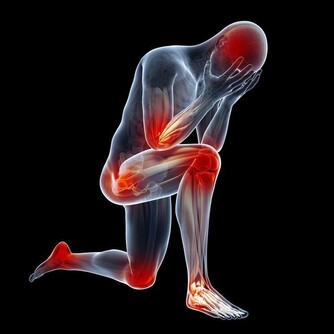

30歲開始,關節痠、痛、軟!

關節退化,是免不了的老化過程。

運動過度、關節受傷、過度肥胖等,都會使關節提早退化,

而膝關節、髖關節、脊椎等,是最容易退化的關節部位。